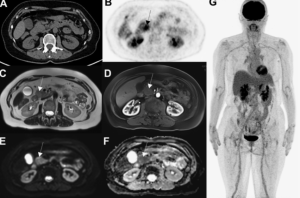

2. Везикулярная стадия (активная). Визуализи - руется полностью выросшая киста или скопление кист (по типу «грозди винограда») в базальных ганглиях, мозжечке, стволе мозга, цистернах или желудочковой системе, в паренхиме полушарий и в субарахноидальных пространствах. Сколекс встречается почти в 50% случаев. НЦЦ по типу «грозди винограда» наблюдается обычно вокруг рострального ствола мозга или сильвиевой щели, обычно лишен сколекса. Отек практически отсутствует (рис. 1).